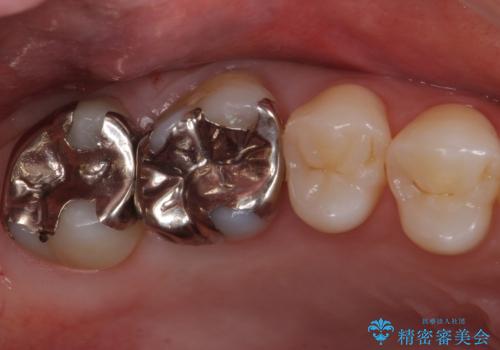

歯と歯の間の虫歯 セラミックインレーでの治療

- 検査の結果、レントゲン画像上で虫歯が確認されたため治療をしていくこととなりました。

白くて精度の高いものをご希望されたためセラミックインレーでの治療を行いました。

- 右上6 セラミックインレー 77,000円費用は治療当時の料金となります

小さな段差もないような適合の良い修復物は他の修復物に比べて今後の虫歯リスクを抑えることができます。